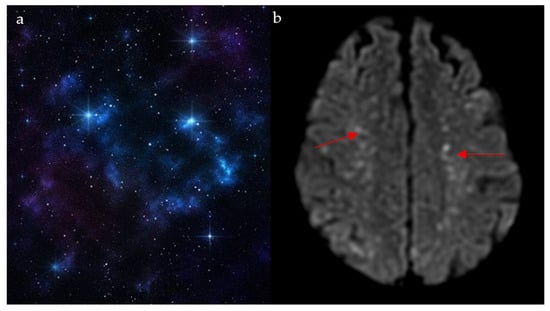

Cosmic Signs in Radiology: A Pictorial Review

Pattern recognition remains a cornerstone of radiologic interpretation, as it facilitates a confident and comprehensive differential diagnosis. Certain pathologies present with specific and highly recognizable patterns on imaging modalities. These patterns can resemble familiar real-life phenomena, including cosmic bodies that surround us. We present in this article a compilation of radiologic signs across various modalities that take inspiration from cosmic phenomena. For each sign, we summarize its defining imaging appearance, typical clinical context, and common pitfalls; where available, we note diagnostic performance (e.g., sensitivity/specificity) to guide appropriate weighting in practice. By coupling memorable imagery with succinct clinical guidance, this pictorial review aims to support a faster, more accurate pattern recognition that is applicable in both low-resource and tertiary care settings, while recognizing that these signs function as educational aids rather than validated diagnostic tests. In familiarizing themselves with these classic signs, training radiologists can benefit from an engaging and memorable way of recognizing various pathological conditions. Full article

Figure 1